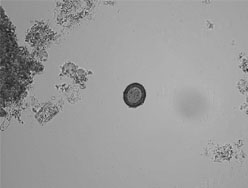

| 〔症例3〕25歳の男性 3週間のインド旅行中から水様性下痢と腹痛があったが通常の生活を行い、1999年3月30日当院内科を受診した。 受診時の検査結果は、CRPが陽性であるが生化学、血液検査ともに基準値内であった(表3)。 便培養検査の依頼以外に、細菌検査室でインド旅行中からの患者の症状(水様性下痢)からクリプトスポリジウム症を疑い、抗酸染色が施行された。一方、細菌検査室から連絡を受けて一般検査室でショ糖遠心沈殿浮遊法とMGL法が行われた。ショ糖遠心沈殿浮遊法で真菌大のピンク色に輝くようなクリプトスポリジウムのオーシストとMGL法でジアルジア(ランブル鞭毛虫)嚢子を検出した(図3、4)。 |

![]() 図3 クリプトスポリジウム 抗酸染色法 |